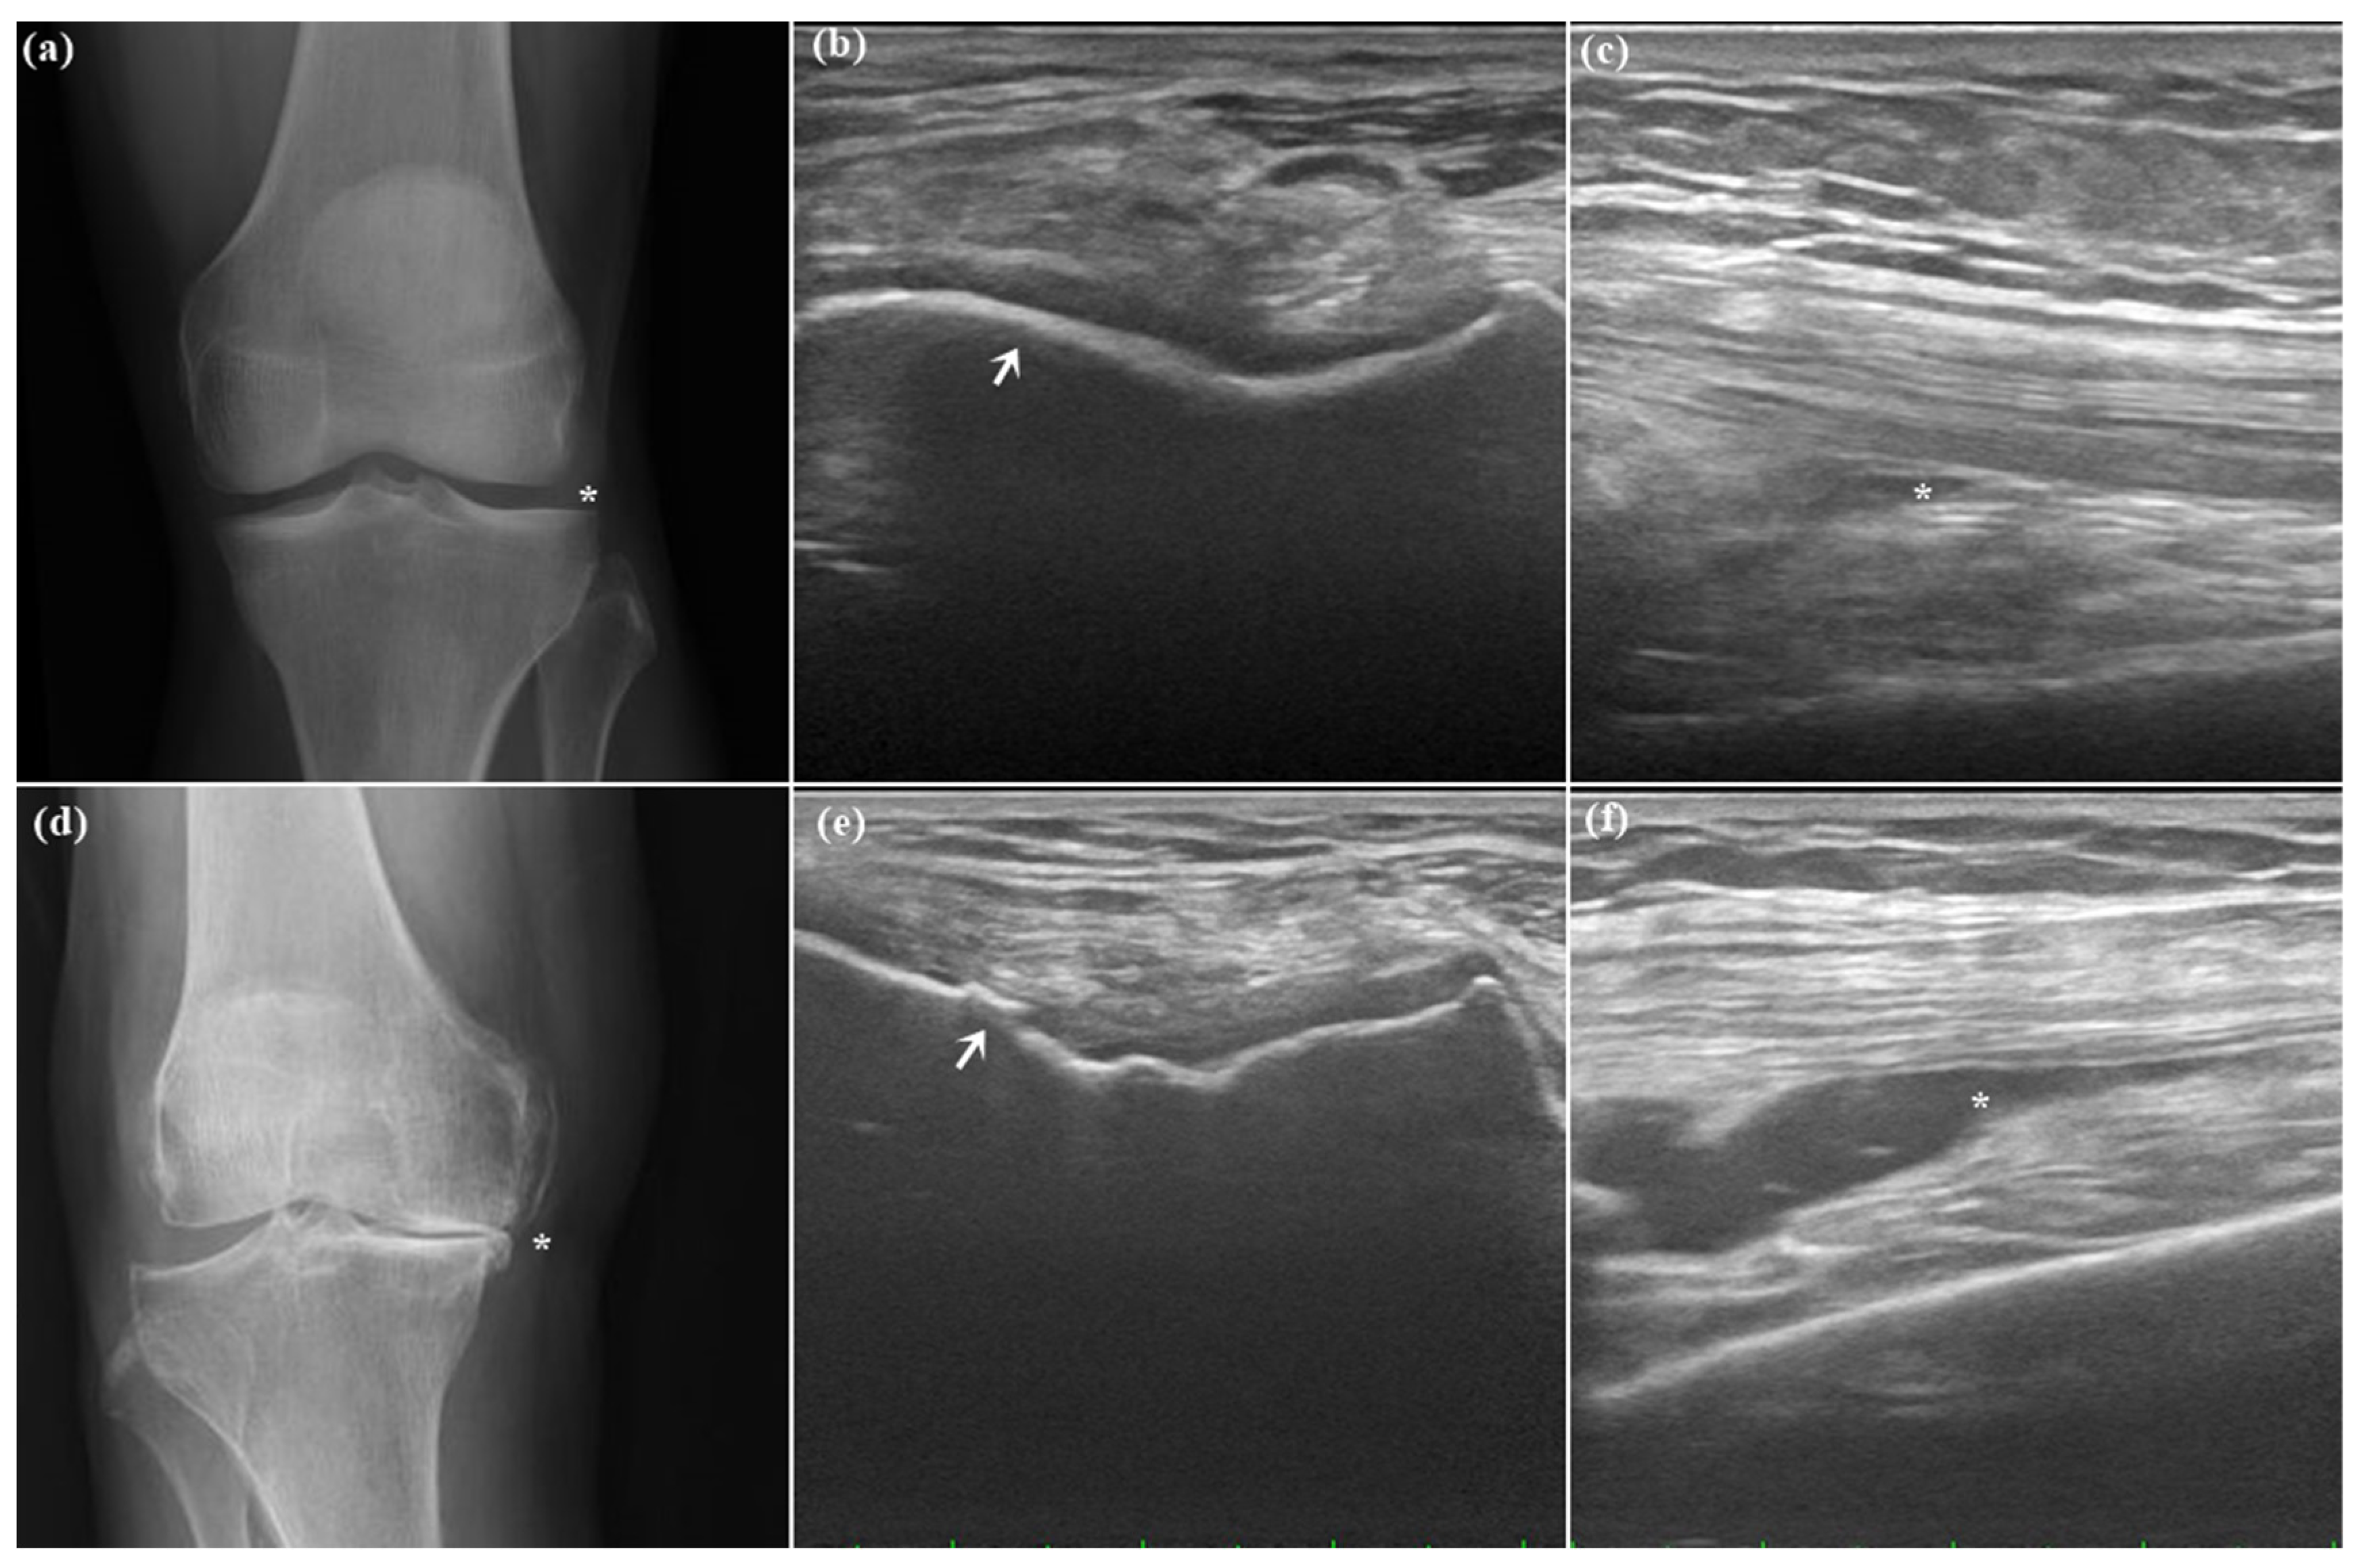

2.1. Patient Characteristics

2.2. Ultrasound Synovial Outcome

4.3. Ultrasound Evaluation